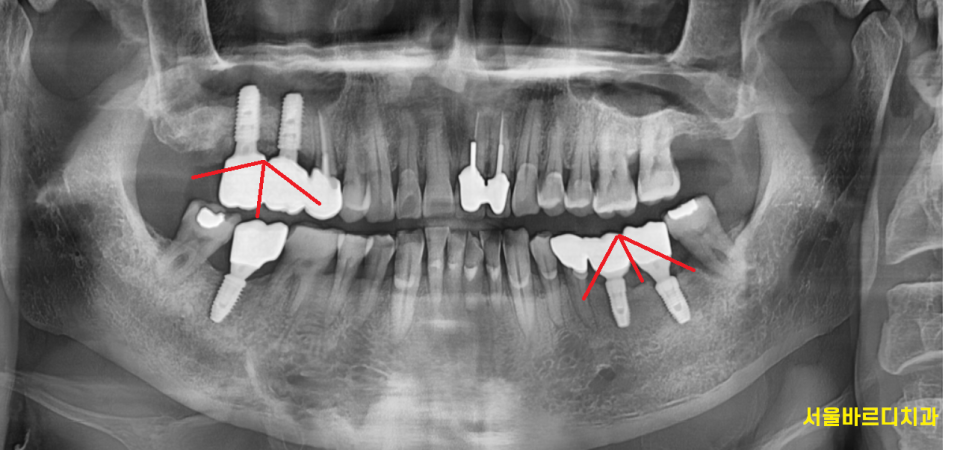

쉽게 얘기하여

임플란트를 좀 숨쉬게 할 구멍을 만들어주는 것입니다.

힘을 덜어준다는 것인데요.

자연치아의 경우 치주인대라는 조직이 있어서

힘을 분산해줄 친구가 있습니다.

임플란트는 인공적인 구조물이다 보니

친구가 없어요~

혼자서 일을 해내야하는데요.

묶어서 제작하게 되면

친구가 생기죠~?

그래서 힘을 분산하게 됩니다.

임플란트 가해지는 무리한 힘을 분산해주어

좀 더 오래 쓸 수 있게 해주어요.

수명을 연장시켜 준답니다.

음식물이 덜 낀다는 장점도 있고요.